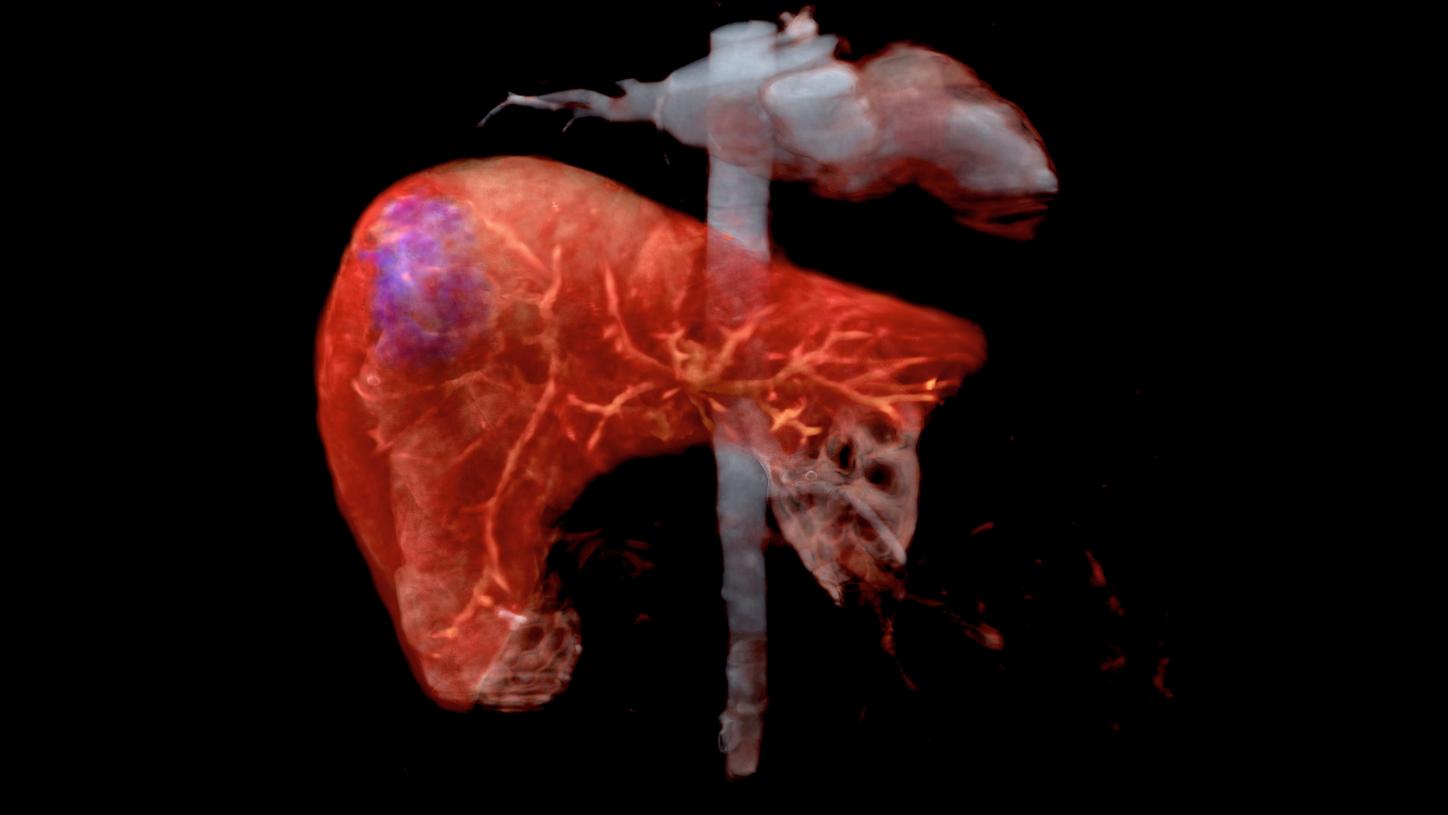

Already today, we cover many clinical topics and tailor our radiology products and solutions along clinical pathways. With intelligent, digitally connected imaging solutions you can improve diagnostic accuracy, plan treatment options and guide minimally invasive therapy. With our focus towards the world’s major diseases including stroke, coronary artery disease, lung, and liver cancer, we are committed to supporting patients in every step of their journey.